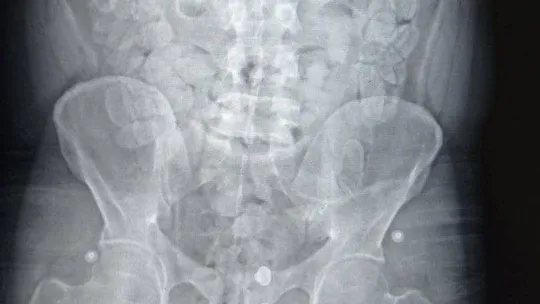

Türkiye’ye midesinde uyuşturucu maddeleri soktuğu tespit edilen zanlı, ardından Yalova Devlet Hastanesi’ne götürüldü. Tomografi cihazı ile gerçekleştirilen iç beden görüntüleme muayenesinde şahsın mide ve bağırsağında çok sayıda kapsül olduğu tespit edildi. Şüpheli, sağlık durumu da göz önünde bulundurularak 3 gün hastanede tutuldu. Tıbbi gözlem sürecinde zanlının mide ve sindirim sisteminde bulunan 155 kapsül reçine esrar daha çıkarıldı.